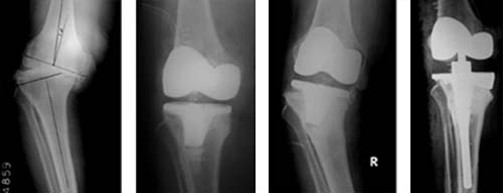

Приклад 1. Хвора Б. 52 років. Діагноз: Ревматоидній Деформівний IVст. гонартроз, вальгусна деформація колінногосуглоба.  Нестабільність та руйнування компонентів ендопротеза. Хворій виконано ревізійне ендопротезування: видалення компонентів ендопротезу, виявлений дефект латерального  виростку великогомілкової кістки тип Т3А за класифікацією АОRI [G.A. Engh, C.H. Rorabeck, 1997]. Під час операції виконана кісткова пластика дефекту латерального виростка лівої великогомілкової кістки. Використаний ендопротез колінного суглоба з подовжувачами .

Приклад 2. Хвора  М. 68 років. Діагноз: лівобічний деформівний IVст. гонартроз, стан після ТЕП лівого КС (2014р.). Під час виконання оперативного втручання компоненти ендопротезу встановлені в варусному положенні. Асептична нестабільність компонентів ендопротеза, тотальна  нестабільність зв’язкового апарату компонентів колінного суглоба (2017 р.)  Хворій виконано ревізійне ендопротезування: видалення компонентів ендопротезу, виявлений дефект виростку великогомілкової кістки тип Т2А за класифікацією АОRI [G.A. Engh, C.H. Rorabeck, 1997]. Враховуючи стан зв’язкового апарату використаний зв’язаний ендопротез типу Hinch.

Приклад 3. Хвора К. 52 років. Діагноз: Деформівний IVст. гонартроз, стан після ТЕП лівого КС (2013р.). ІМТ хворої складає 35 балів. Асептична нестабільність компонентів ендопротеза лівого колінного суглоба, міграція великогомілкового компоненту (2017 р.) (рис. 2 а). Хворій виконано ревізійне ендопротезування: видалення компонентів ендопротезу, виявлений дефект медіального виростку великогомілкової кістки тип Т3А за класифікацією АОRI [G.A. Engh, C.H. Rorabeck, 1997]. Під час операції виконана кісткова пластика дефекту. Використаний ендопротез колінного суглоба з подовжувачами.

Приклад 4. Хвора Г. 72 років. Діагноз: Деформівний IV ст. гонартроз, стан після ТЕП КС (2010р.). Гемартроз в післяопераційному періоді, хронічний синовііт.Септична нестабільність компонентів ендопротеза  колінного суглоба на протязі року. Виявлений дефект виростків стегнової кістки  тип Т3, F 3 за класифікацією АОRI [G.A. Engh, C.H. Rorabeck, 1997]. Хворій виконано  двоєтапне ревізійне ендопротезування: видалення компонентів ендопротезу іплантовано спейсер з антибіотиком. Піcля санаціїї виконано другий єтап певізії, імплантовано ревізійний ендопротез колінного суглоба.